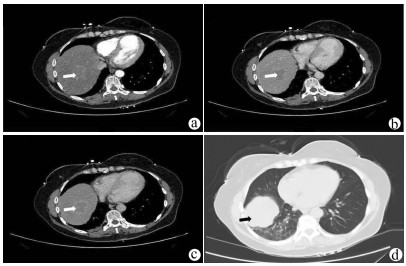

A case of primary splenic angiosarcoma

Huijun WANG, Jianxiang NIU, Xiaoyan XU, Weihua ZHENG, Pengfei LI, Yibo LIU, Junjing ZHANG

2021, 37(11): 2655-2657. DOI: 10.3969/j.issn.1001-5256.2021.11.036

Abstract(840) HTML (477) PDF (3488KB)(69)

Abstract: